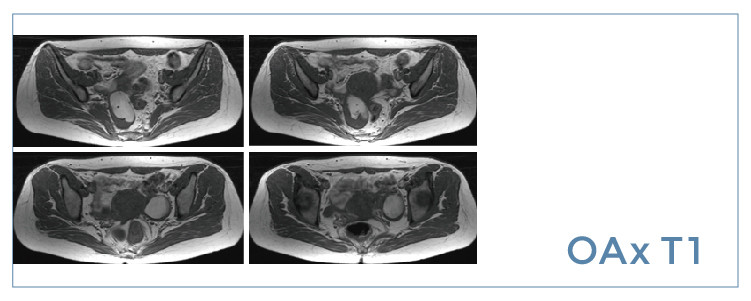

【朗润影像档案】20190802磁共振影像病例结果讨论

【朗润影像档案】磁共振影像病例分享(编号20190802)